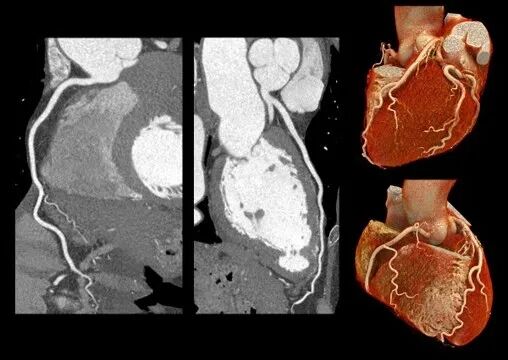

冠状动脉成像

精细细节、血管连续性好、超薄层厚

🔹在心血管成像中,CZT-PCCT通过更高的空间分辨率与更薄层厚成像能力,使血管细节及远端分支结构获得更清晰、连续的显示。对于小血管及复杂病变的观察,有助于提升影像评估的精细度,为心血管疾病的诊断与分析提供更加可靠的依据。